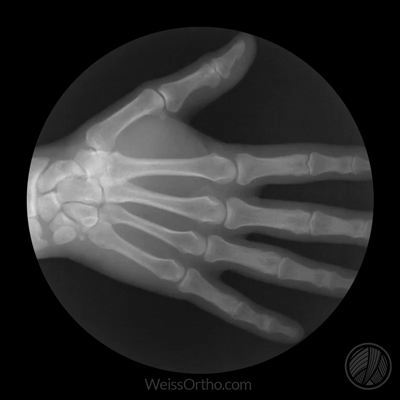

Met X-rays of Röntgenstralen kunnen we in ons lichaam kijken, maar we kennen het meestal gewoon als een foto: een stilstaand beeld van botten of gewrichten. Door fluoroscopie kunnen echter ook bewegende beelden gemaakt worden.

Ontwerper en fotograaf Cameron Drake ging aan de slag met beelden van het orthopedisch instituut van Dr. Noah Weiss in de V.S. (Weis Orthopaedics). Op zijn blog legt Drake uit hoe hij de beelden die Dr. Weiss gemaakt heeft van zijn patiënten omgezet heeft in deze gifs.